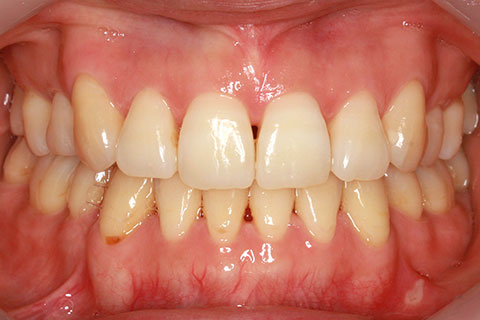

ハーフリンガル矯正1:上の歯のみ舌側矯正で治療(矯正期間20ヶ月)

- 年齢・性別

- 22歳女性

- 治療期間

- 1年8ヶ月

- 抜歯

- 上顎4番抜歯

- 治療費

- 110万円(税込み)

- 備考

- ハーフリンガル矯正

- 治療内容

- 上下前歯部凸凹の改善

- 施術の副作用(リスク)

- 裏側矯正では装置に慣れるまで発音しづらい場合がある。矯正治療に伴うリスクと治療限界についてはこちらをお読みください。